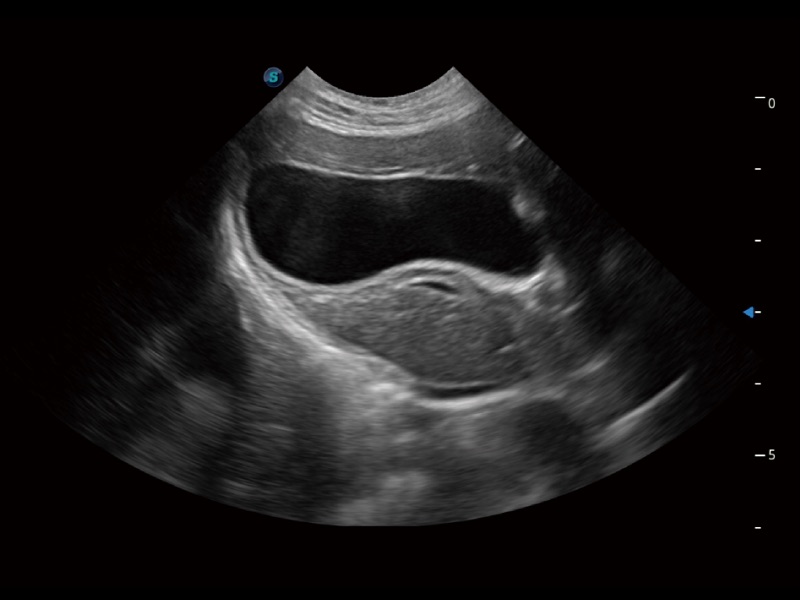

一鍵自動(dòng)識(shí)別膀胱壁及自動(dòng)測(cè)量膀胱容積,不受膀胱形狀和大小的限制,幫助醫(yī)生快速精準(zhǔn)獲得測(cè)量的數(shù)據(jù)。

ProPet 70專(zhuān)為動(dòng)物醫(yī)生設(shè)計(jì),對(duì)不同的動(dòng)物體型和生理結(jié)構(gòu)作出了針對(duì)性的優(yōu)化。通過(guò)動(dòng)物影像專(zhuān)用軟件,可滿(mǎn)足個(gè)性化的應(yīng)用需求,幫助動(dòng)物醫(yī)生獲得更精確的診斷數(shù)據(jù)。

ProPet 70 全新的動(dòng)物超聲智能軟件和豐富的探頭群,為動(dòng)物醫(yī)生提供了高清晰度和精細(xì)分辨率的圖像,無(wú)論在寵物、馬科、畜牧還是實(shí)驗(yàn)室動(dòng)物等應(yīng)用中都可以輕松應(yīng)對(duì),為您的日常工作帶來(lái)滿(mǎn)意的體驗(yàn)。